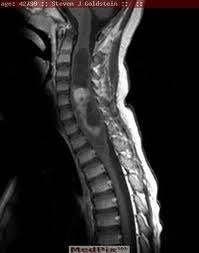

Spinal astrocytoma

A cystic mass affecting the cord with a long segment, suggestive of astrocytoma.

MRI T2 image clearly suggests the cystic nature of the mass.

Ring enhancement of the mass with enhancing nodules.